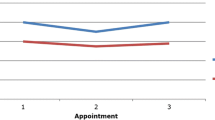

Across all investigated patients, pituitary surface was convex in 16 (10 in the NTHG and 6 in the THG) and planar in six (5 in the NTHG and 1 in the THG). In none of the patients, indirect signs of pituitary adenoma such as a deviation of the pituitary stalk or bony enlargement/arrosion of bony sella and adjacent bone structures were present. In the NTHG, midsagittal pituitary height was 8.9 ± 1.7 mm (range 6.3–12.6 mm) and pituitary volume 460.3 ± 133.4 mm3 (range 260.8–644.0 mm3). In the THG patients, postsurgical pituitary midsagittal height and volume amounted to 8.2 ± 0.9 mm, range 6.1–13.2 mm and 411.5 ± 55.2 mm3, range 231.8–679.5 mm3, respectively. Pituitary size and volume did not statistically differ between the NTHG and the THG (all Z ≤ − 1.48, all p ≥ 0.138) (see Table 1).

Moreover, in five patients in the THG, pre- and postoperative MRIs could be analyzed. In this small subgroup, pituitary surface was concave before brain tumor treatment and shunt implantation, but planar or convex in the follow-up MRIs. Pituitary measurements preoperatively were 2.54 ± 1.0 mm, range 1.4–4.2 mm (pre-operative midsagittal height) and 120.5 ± 69.2 mm3, range 82.3–230.7 mm3 (pre-operative pituitary volume) as compared to 6.6 ± 0.7 mm, range 5.8–7.7 mm (post-operative midsagittal height) and 368.9 ± 57.9 mm3, range 329.5–465.7 mm3 (post-operative pituitary volume) 1 year after surgery. This difference was statistically significant (Z = − 2.02, p = 0.043) (see Table 2).

Since pituitary size and volume did not statistically differ between the NTHG and the THG, the comparison with the published age-matched healthy population mean was performed with the entire patient cohort (mean midsagittal height 8.5 ± 0.3 mm, range 6.1–13.2 mm, mean pituitary volume 444.8 ± 29.0 mm3, range 231.8–679.5 mm3). As expected, pituitary height (t = 5.91; p < 0.001) and volume (t = 3.03; p = 0.006) in the shunted hydrocephalus patients differed (highly) significantly to the averaged population mean [8]. Mean pituitary height and volume of those patients with clinical signs of CSF overdrainage did not differ significantly from those without (all Z ≤ − 1.56, all p ≥ 0.119). Figure 2 shows the change of pituitary morphology in a NTHG patient, while Fig. 3 illustrates the changed sellar floor morphology and pituitary hyperemia.